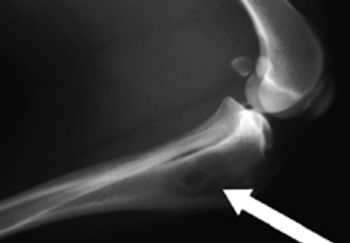

A general review of osteosarcoma then discuss various novel therapies currently available for the local and systemic treatment of this cancer in dogs.